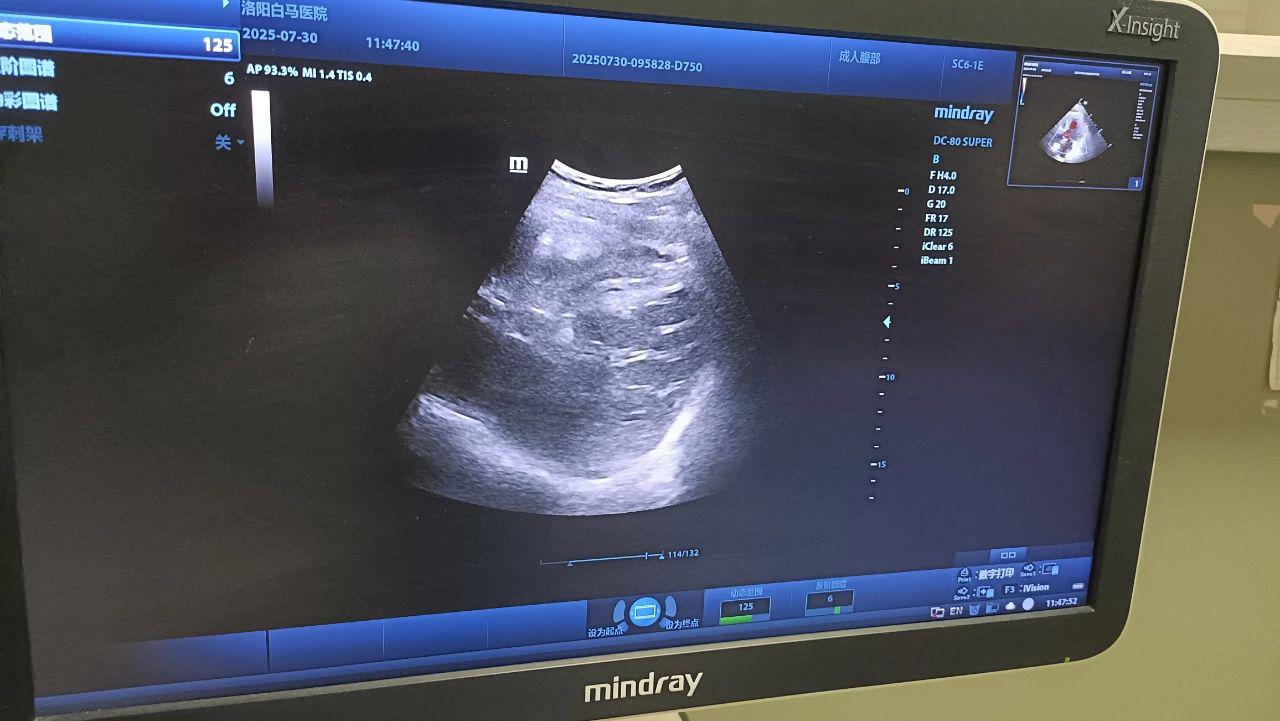

日前,87岁的高大娘,突发急性胆囊炎,紧急来到洛阳白马医院。由于患者高龄,并有严重的心脏病,心率只有38次/分,胆囊结石嵌钝,胆囊梗阻化脓,必须手术。普外科的吕伟子主任、苏东医生对高阿姨的情况进行了系统的分析与讨论,但考虑到手术禁忌,最终决定为她实施超声引导下经皮胆囊穿刺置管引流术(PTGD)。

超声引导下经皮胆囊穿刺置管引流术(Percutaneous Transhepatic Gallbladder Drainage, PTGD)是一种通过超声定位引导,经皮经肝穿刺胆囊并置入引流管,引流淤积的胆汁及脓液,从而缓解胆囊壁水肿、缺血,控制感染进展以缓解胆囊急性炎症、降低胆囊内压力的微创介入技术。该技术具有操作简便、创伤小、安全性高的特点,尤其适用于高龄、合并严重基础疾病或无法耐受外科手术的急性胆囊炎患者。

在与患者及家属进行充分沟通并取得同意后,我院普外科吕伟子主任,苏东医生。在超声科王英主任的全力协助下,成功完成了超声引导下胆囊穿刺置管术。患者无明显不适,术后恢复良好。